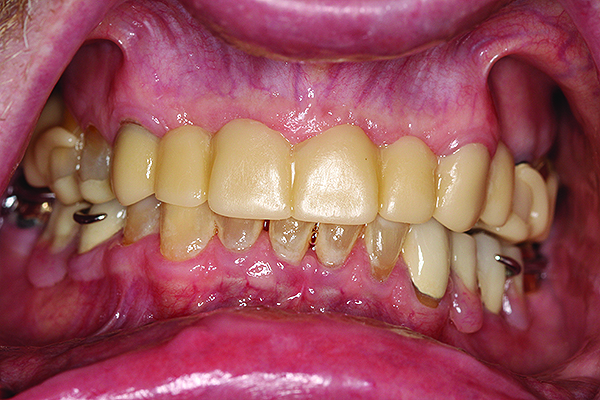

After a successful framework try-in, a maxillomandibular record was obtained, denture teeth (BlueLine® DCL Esthetic Denture Teeth, Ivoclar Vivadent, www.ivoclarvivadent.com) were set to a lingualized occlusal scheme, and a denture wax try-in was completed clinically (Figure 10).

After the denture wax try-in appointment and patient approval, the RPDs were processed and inserted, and necessary clinical adjustments were made (Figure 11, Figure 12, Figure 13)

Fig 10. Denture wax try-in of maxillary and mandibular RPDs.

Figure 10